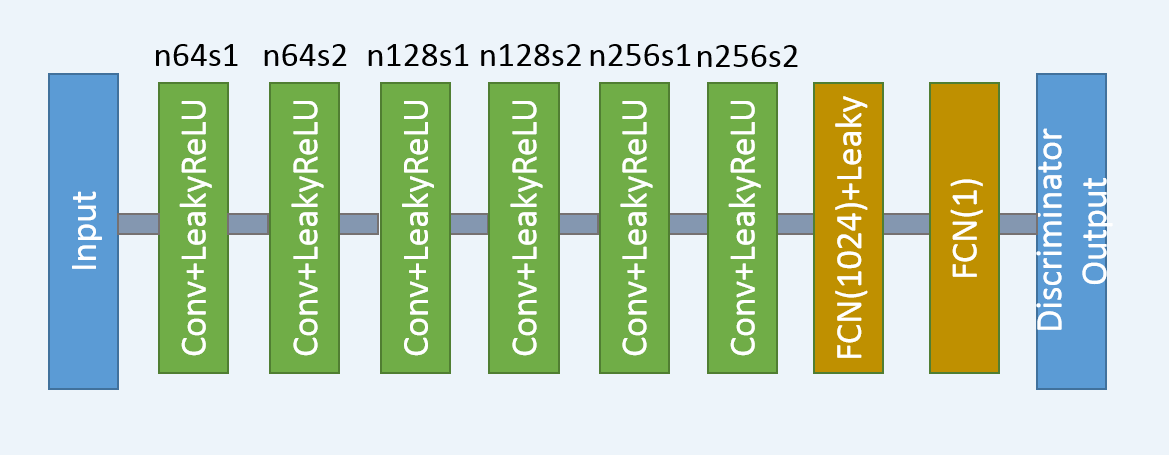

The third part of the network is the discriminator . As shown in Fig. 2, has 6 convolutional layers with the structure inspired by others’ work [43, 29, 30]. The first two convolutional layers have 64 filters, then followed by two convolutional layers of 128 filters, and the last two convolutional layers have 256 filters. Following the same logic as in , all the convolutional layers in have a small kernel size. After the six convolutional layers, there are two fully-connected layers, of which the first has 1024 outputs and the other has a single output. Following the practice in [31], there is no sigmoid cross entropy layer at the end of .